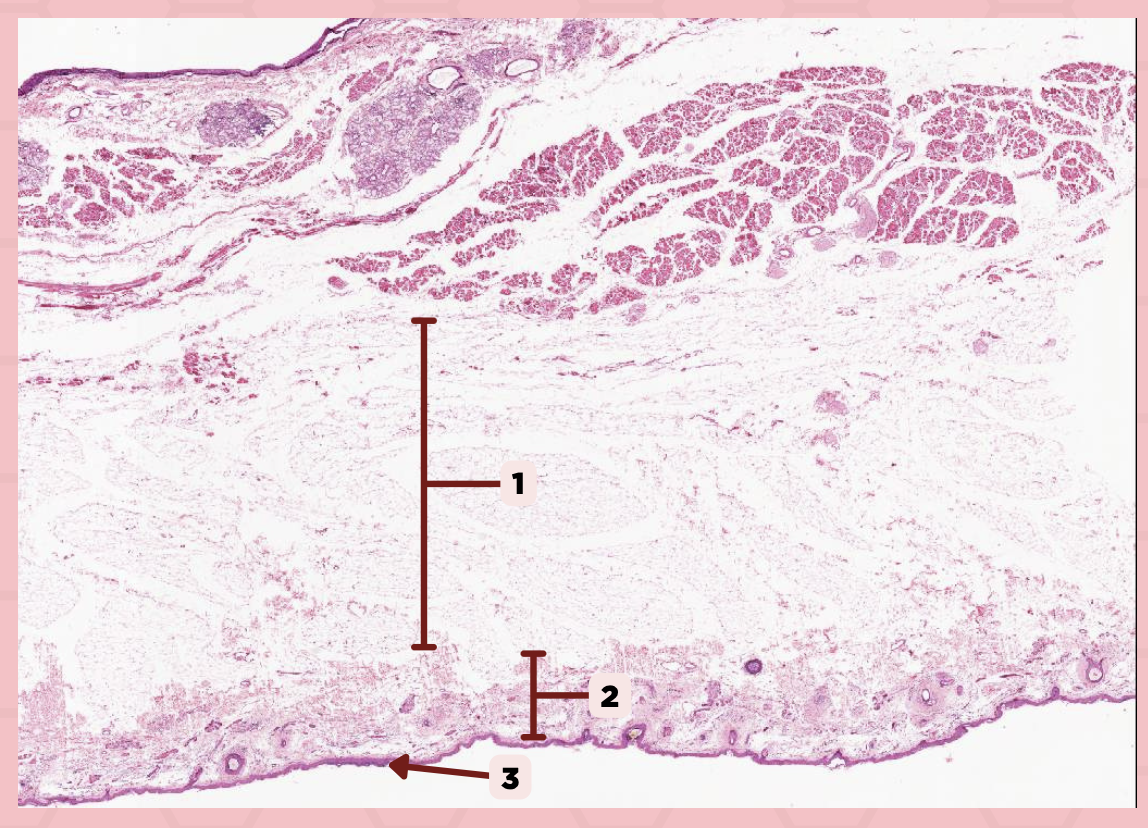

Lip

What is the specimen showed in the picture?

Epidermis

Identify the structure labeled as 1.

Dermis

Identify the structure labeled as 2.

Arrector Pilli Muscle

Identify the structure labeled as 3.

Hair Follicle

Identify the structure labeled as 4.

Sebaceous Glands

Identify the structure labeled as 5.

Lip

What specimen is showed in the picture?

Labial Glands (in the Mucosa)

Identify the structure labeled as 1.

Skeletal Muscle Cells

Identify the structure labeled as 2.

Lamina Propria

Identify the structure labeled as 3.

Mucosa

Identify the structure labeled as 4.

Lip

What specimen is showed in the picture?

Skeletal Muscle Fibers

Identify the structure labeled as 1.

Labial Glands

Identify the structure labeled as 2.